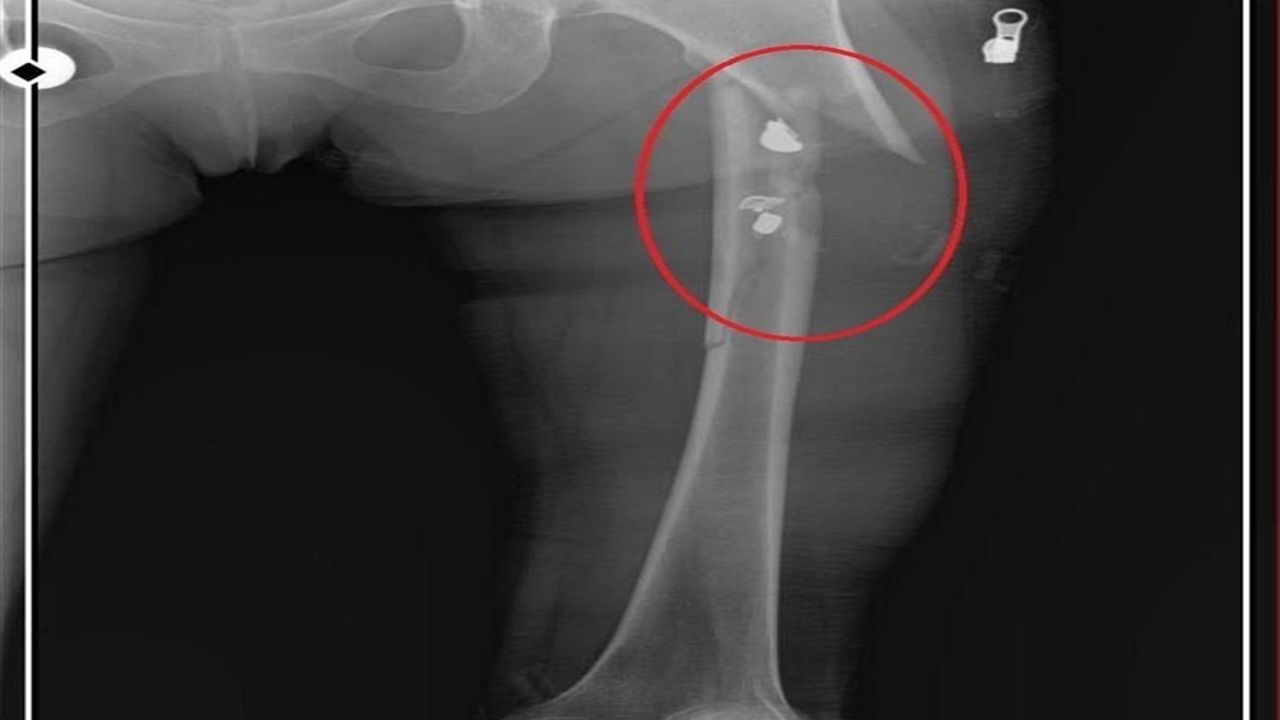

Osmangazi ilçesi Küplüpınar Mahallesi'nde 2023 Haziran ayında meydana gelen olayda; İlyas Sarıkaya, mahalleden arkadaşı Recep Özaslan'ı, Alzheimer hastası annesi A.S. ve sevgilisi Fatma O. ile birlikte yaşadığı eve çağırdı. İddiaya göre; uyuşturucu etkisinde olan Sarıkaya, sevgilisiyle ilişkisi olduğunu düşündüğü Özaslan'ı tabancayla vurdu ardından da 'acı çekmesin' diye 2 kez daha ateş etti. Özaslan, beline ve göğsüne isabet eden kurşunlarla olay yerinde hayatını kaybetti.

İlyas Sarıkaya, sevgilisi Fatma O.'yu da 8 kurşunla vurup, yaraladı. Arkadaşı Özaslan'ın cesedini önce çarşafa sonra da streç filme sarıp bantlayan Sarıkaya, eczaneden aldığı sargı bezi ve ilaçlarla pansumanını yaptığı sevgilisine yaralı haldeyken 21 gün boyunca cinsel saldırıda bulundu.